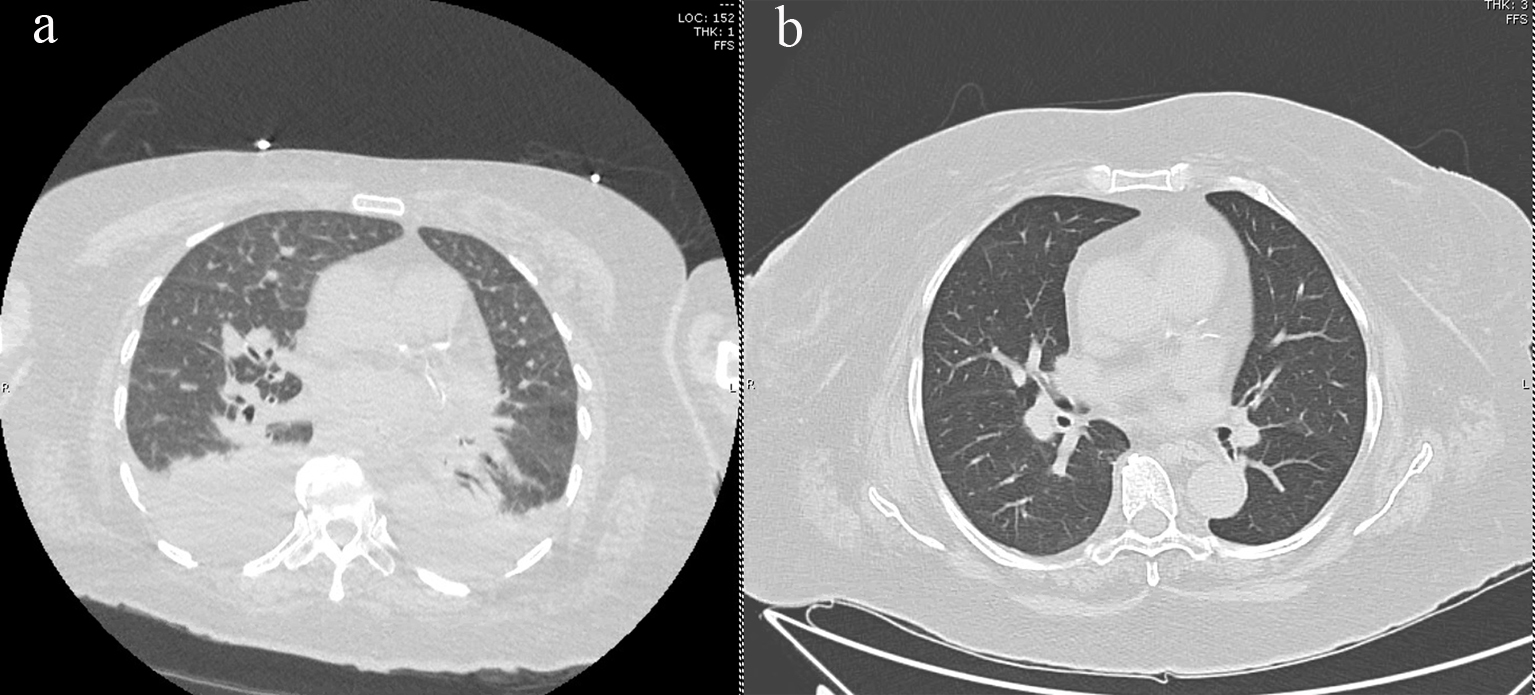

Seven months post-transplant, the patient was hospitalized for worsening shortness of breath and worsening hypoxemia without fevers or leukocytosis. Blood cultures were negative and induced sputum grew normal respiratory flora. Infectious workup was also negative for Pneumocystis jirovecii, aspergillus, Epstein-Barr virus, cytomegalovirus, and a respiratory viral panel. Pulmonary function test (PFT) showed no evidence of pulmonary obstruction. At the time of admission, the patient was taking rivaroxaban for pulmonary embolism, but entilation/perfusion (V/Q) scan showed no evidence of new embolus. High-resolution computed tomography (HRCT) of the chest showed bilateral smooth interlobular septal thickening with scattered ground glass opacities and pulmonary interstitial edema (Fig. 1a). Brain natriuretic peptide (BNP) was 140 pg/mL. Transthoracic echocardiogram (TTE) showed an ejection fraction of 61% and right ventricle systolic pressure elevated to 55 mm Hg. A bubble study did not show evidence of shunting.

![]() Click for large image | Figure 1. (a) HRCT of thorax demonstrating bilateral pleural effusions, scattered ground glass opacities, and interlobular septal thickening, and (b) HRCT showing resolution of ground glass opacities and pulmonary edema after midostaurin cessation. HRCT: high-resolution computed tomography. |

Midostaurin was stopped due to concern of drug-related interstitial lung disease, and subsequently, the patient’s symptoms started improving. Biopsy could not be conducted due to a high risk of bleeding. The patient was diuresed with furosemide and a pulmonary consult recommended starting the patient on prednisone. Repeat HRCT chest 3 months later showed interval resolution of pulmonary edema as well as decrease in lower lobe ground glass opacities (Fig. 1b). Repeat echocardiogram showed improvement in right ventricular systolic pressure to 45 mm Hg. During the course of the treatment, the patient developed pulmonary hypertension with right heart strain that was improved on diuresis with furosemide. She was started on pulmonary hypertension medications sildenafil and macitentan. The respiratory symptoms continued improving, and the steroids were slowly tapered off. The patient’s C-reactive protein (CRP) peaked to 70 mg/dL and normalized at 2.3 mg/dL, and lactate dehydrogenase (LDH) reached a level of 300 U/L and normalized at 199 U/L. The patient continued to be in complete remission, maintaining full chimerism 19 months post-transplant.

Drug-induced lung disease, often a diagnosis of exclusion, is associated with both antineoplastic and non-neoplastic agents. The most common HRCT findings have been described as ground-glass opacities, which are often found in a diffuse pattern in toxicities associated with antineoplastic agents [8, 9]. In our patient, we observed worsening respiratory status with HRCT findings of interlobular septal thickening and scattered ground glass opacities approximately 7 months after allogeneic stem cell transplant and at a midostaurin dose of 25 mg daily. Cessation of midostaurin and treatment with steroids resulted in significant improvement in both clinical symptoms and radiologic findings within 3 months. To our knowledge, although midostaurin has previously been implicated in pulmonary toxicity, this is the first described case of pulmonary toxicity post-allogeneic transplant [5, 6]. Of note, our patient also received PTCy as prophylaxis against GVHD. As cyclophosphamide is also associated with pulmonary toxicity [8], it is possible that its combination with midostaurin only increased the chances of pulmonary complications. Future directions in understanding the risk of interstitial lung injury associated with midostaurin involve identifying the time after transplant that toxicity is likely to occur, whether toxicity is dose dependent, whether the drug can be safely re-introduced after resolution of symptoms and whether its combination with other agents is feasible and safe.